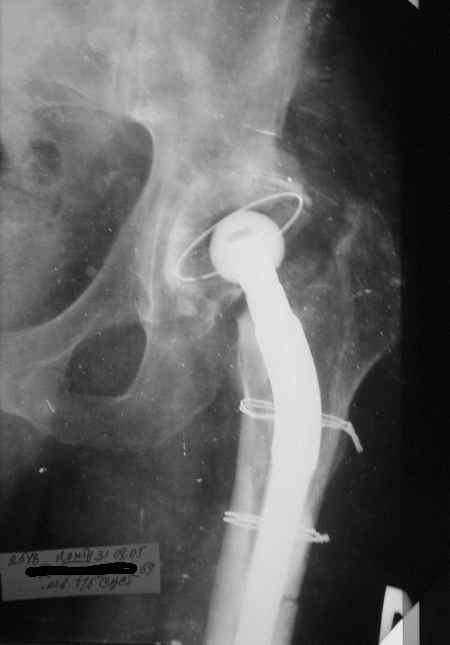

Уважаемые коллеги,Мужчина, 69 лет, в декабре 2004 г перенес тотальную цементную артропластику . Через 3 мес после операции на фоне прогрессирующих болей в средней и проксимальной третях бедра при нагрузке возникли резкие боли и появилось опухолевидное болезненно образование. Процесс сопровождался резким одномоментным укорочением ноги.

В феврале 2005 г. выполнена ревизионная артропластика, завершившаяся прогрессировавшим в течение 1-2 мес укорочением ноги. В настоящее время ходит только с костылями, при движениях в тазобедренном суставе испытывает резкие боли, ощущает хруст. Попытка осевой нагрузки бедра сопровождается ощущением "перемещения поршня" и заметным по внешним ориентирам укорочением левой ноги на 1-1,5 см.

Наверное перфорация стенки при первичном протезировании и неадекватный размер Вагнера при ревизионном? Что-нибудь еще?

И ножка Вагнера подобра плохо, и насчет возможной инфекции Вы совершенно правы, т.к. рана после второй операции заживала вторичным натяжением.

К сожалению, Р-граммы не захватывают полностью бедро, поэтому окончательное решение может быть после полноценного р-ского обследования. Однако думаю, что оптимальное решение - полнопокрытая ножка длинной не менее 200 мм, без привязки к типу протеза. Это может быть модульная система ZMR, Solution и др., главное - принцип. В отношении чашки тоже есть определенные сомнения. Думаю, что наш ин-т (РосНИИТО, СПб) смог бы сделать эту операцию.

Ситуация достаточно несложная. Основной массив бедренной кости сохранён. Лучше поменять чашку сразу, потому что ей не долго осталось жить. Слишком латерально поставлена. Предпочитаю RM чашки при ревизии. Ножка предпочтительней Solution. Если есть проблемы по замене, могу взять к себе без проблем.